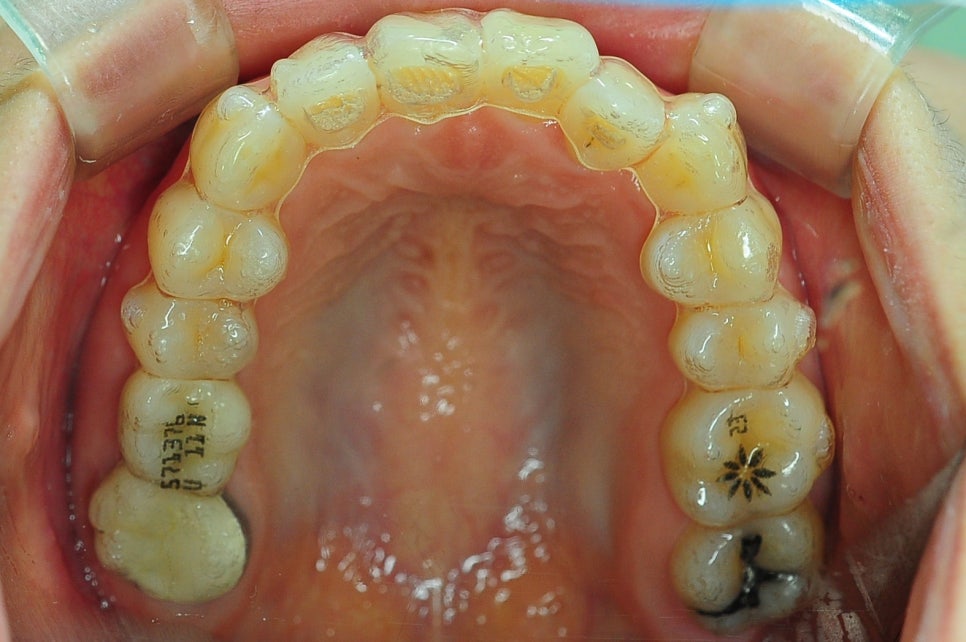

인비절라인 8개월 교정 전후 모습

*치료 기간: 2024.04.21 - 2024.12.22

*치료 전후 사진은 환자의 동의하에 게재하였으며, 동일한 환경과 조건에서 촬영된 전후 사진입니다.

저희 스마일디치과는

3D 스캐너를 활용해 아이의 치열과 구강구조를 정확하게 분석하고,

개인별 맞춤형 교정 계획을 수립합니다.